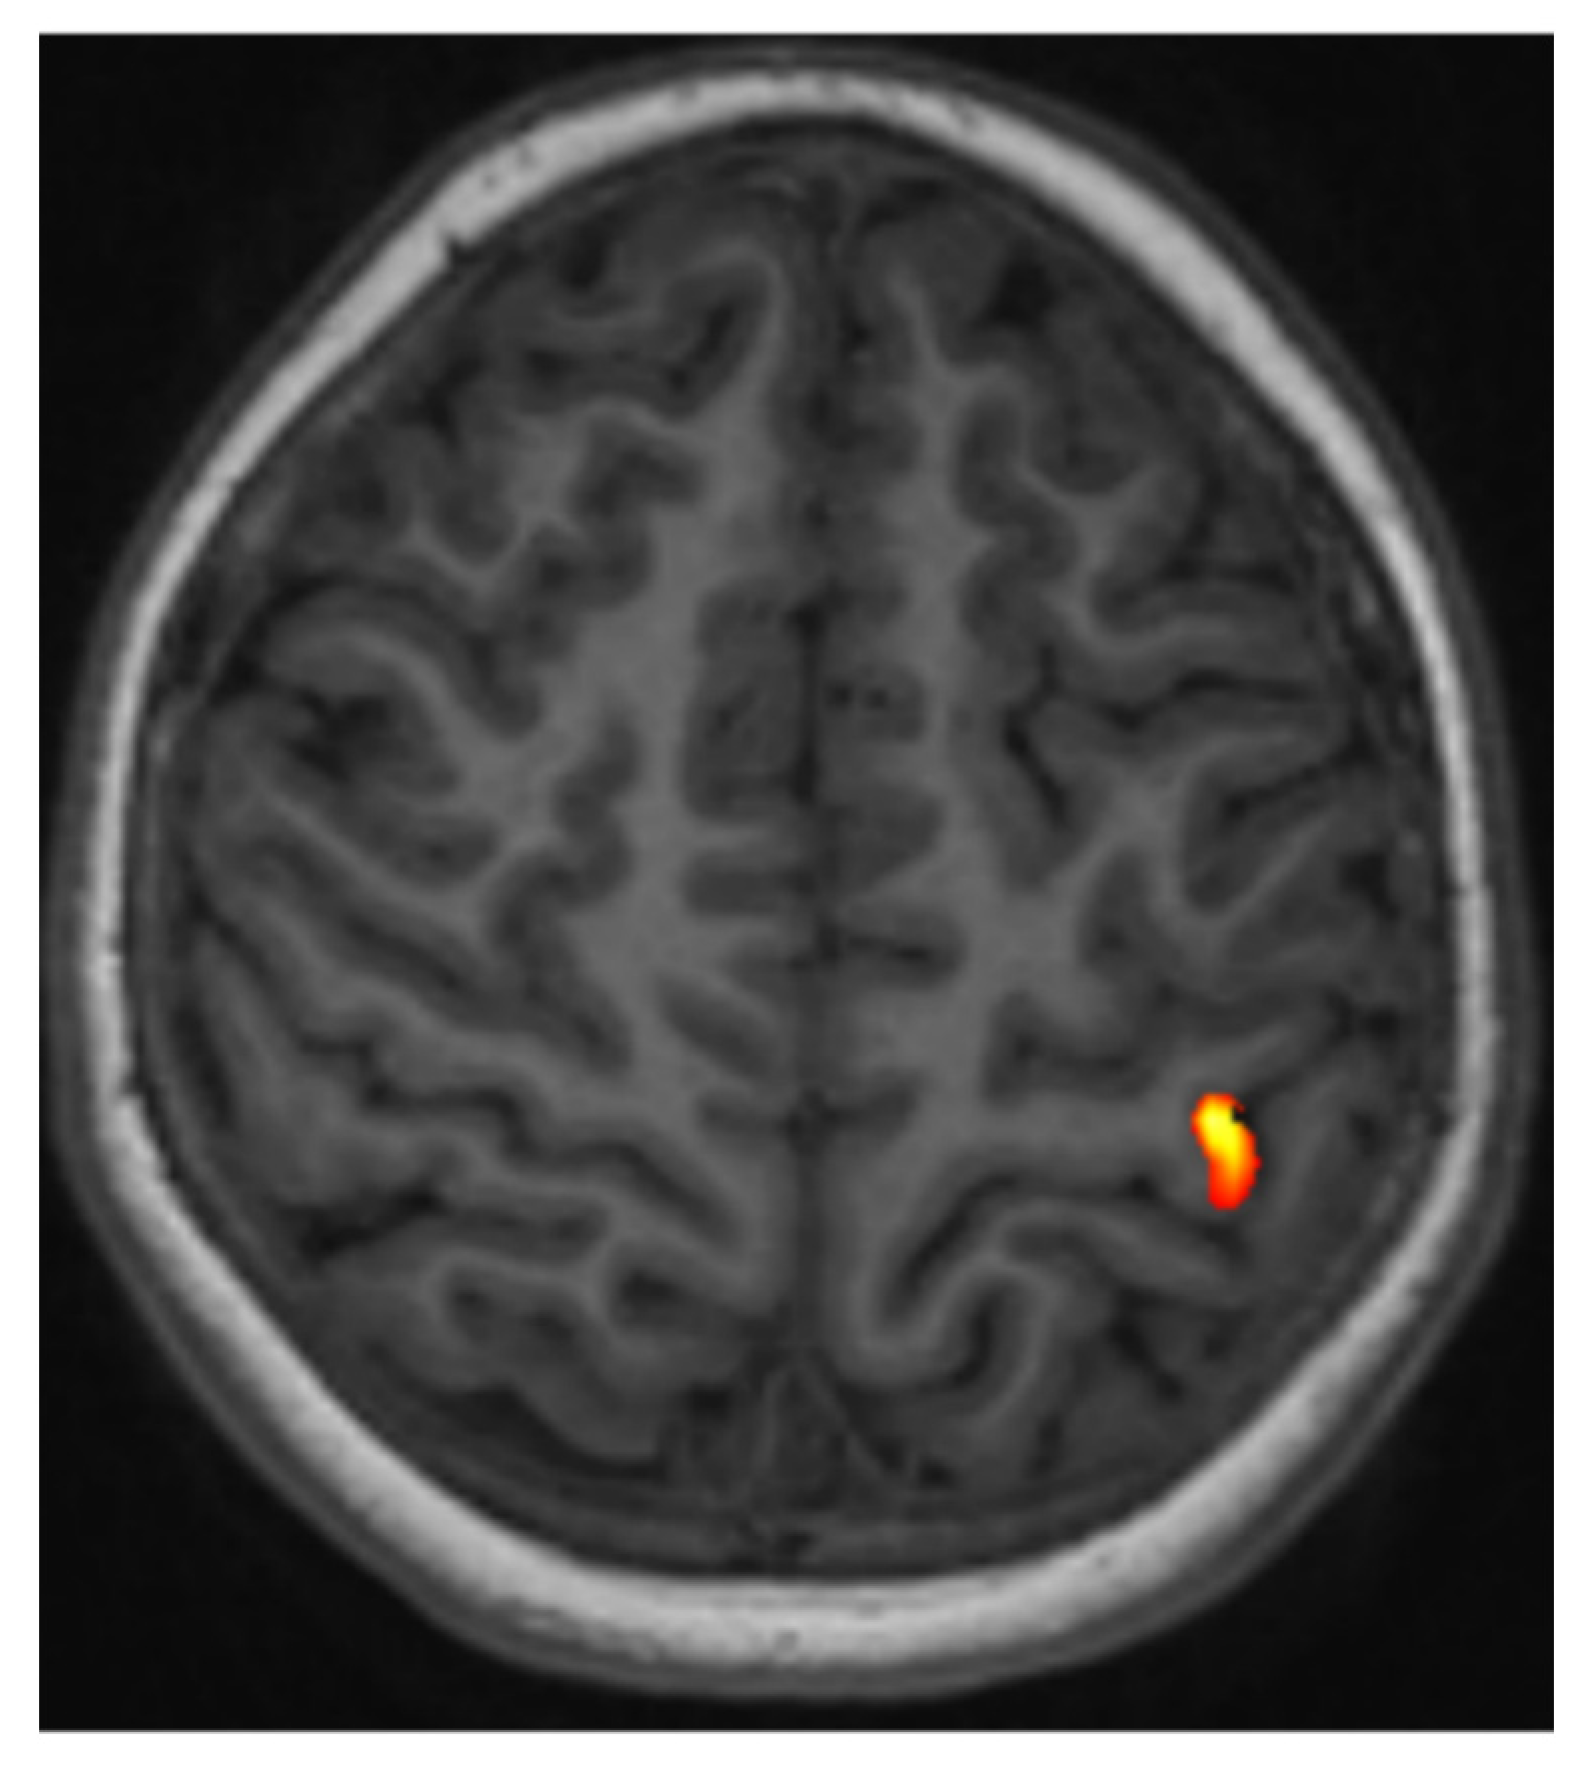

5.1. fMRI of Motor and Somatosensory Functions

- When the anatomy is effaced or partially effaced, and morphological Rolandic landmarks cannot be identified due to tumor growth;

- When a tumor lies in proximity to the identifiable motor hand area.